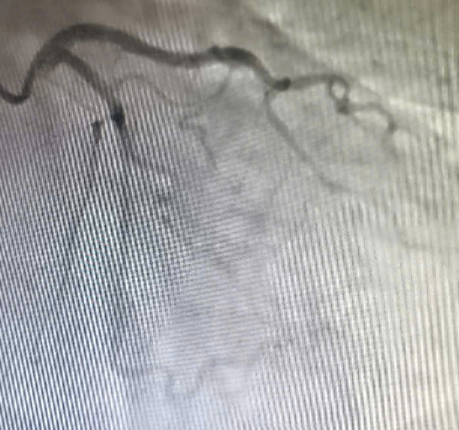

Mặc dù chụp mạch vành không phát hiện tổn thương tắc nghẽn, các bác sĩ tiếp tục quyết định chụp hình ảnh buồng tim. Kết quả cho thấy rối loạn vận động điển hình của hội chứng Takotsubo, với tăng co bóp ở đáy và giảm vận động ở mỏm tim, xác định đây là bệnh cơ tim cấp do căng thẳng.

| Hình ảnh hệ động mạch vành không thấy hẹp tắc - Ảnh BVCC |